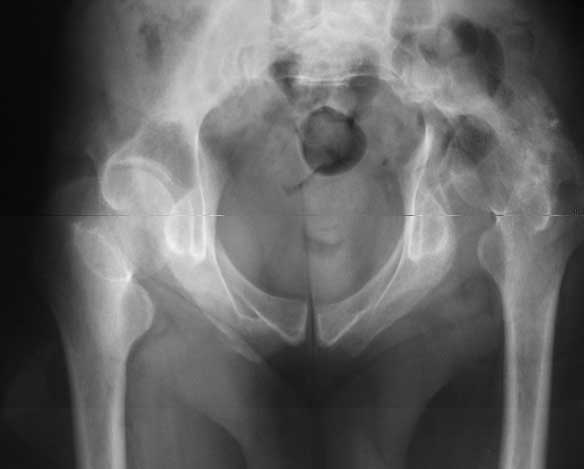

Sorry missed the wide open pubic diastasis.

You could tryan open reduction of the pubis through a Pfannensteil inscision and get some closure done. An external fixator may help preoperatively to get some compression.

I think, if symphysis is unstable at first you must open and stabilize symphysis by plate or

external fixator or may be use both together.